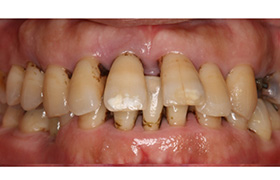

再生療法

(歯周組織再生療法)

歯周病などにより、顎骨や歯根膜を失った際の治療法です。エムドゲインは哺乳類由来のタンパク質で、歯の発生を促す作用があります。骨を失った箇所にエムドゲインを塗布することで、造骨細胞などの歯の周辺を形作る細胞群が活性化されて、顎骨およびその周辺組織が再生されます。

Before

After